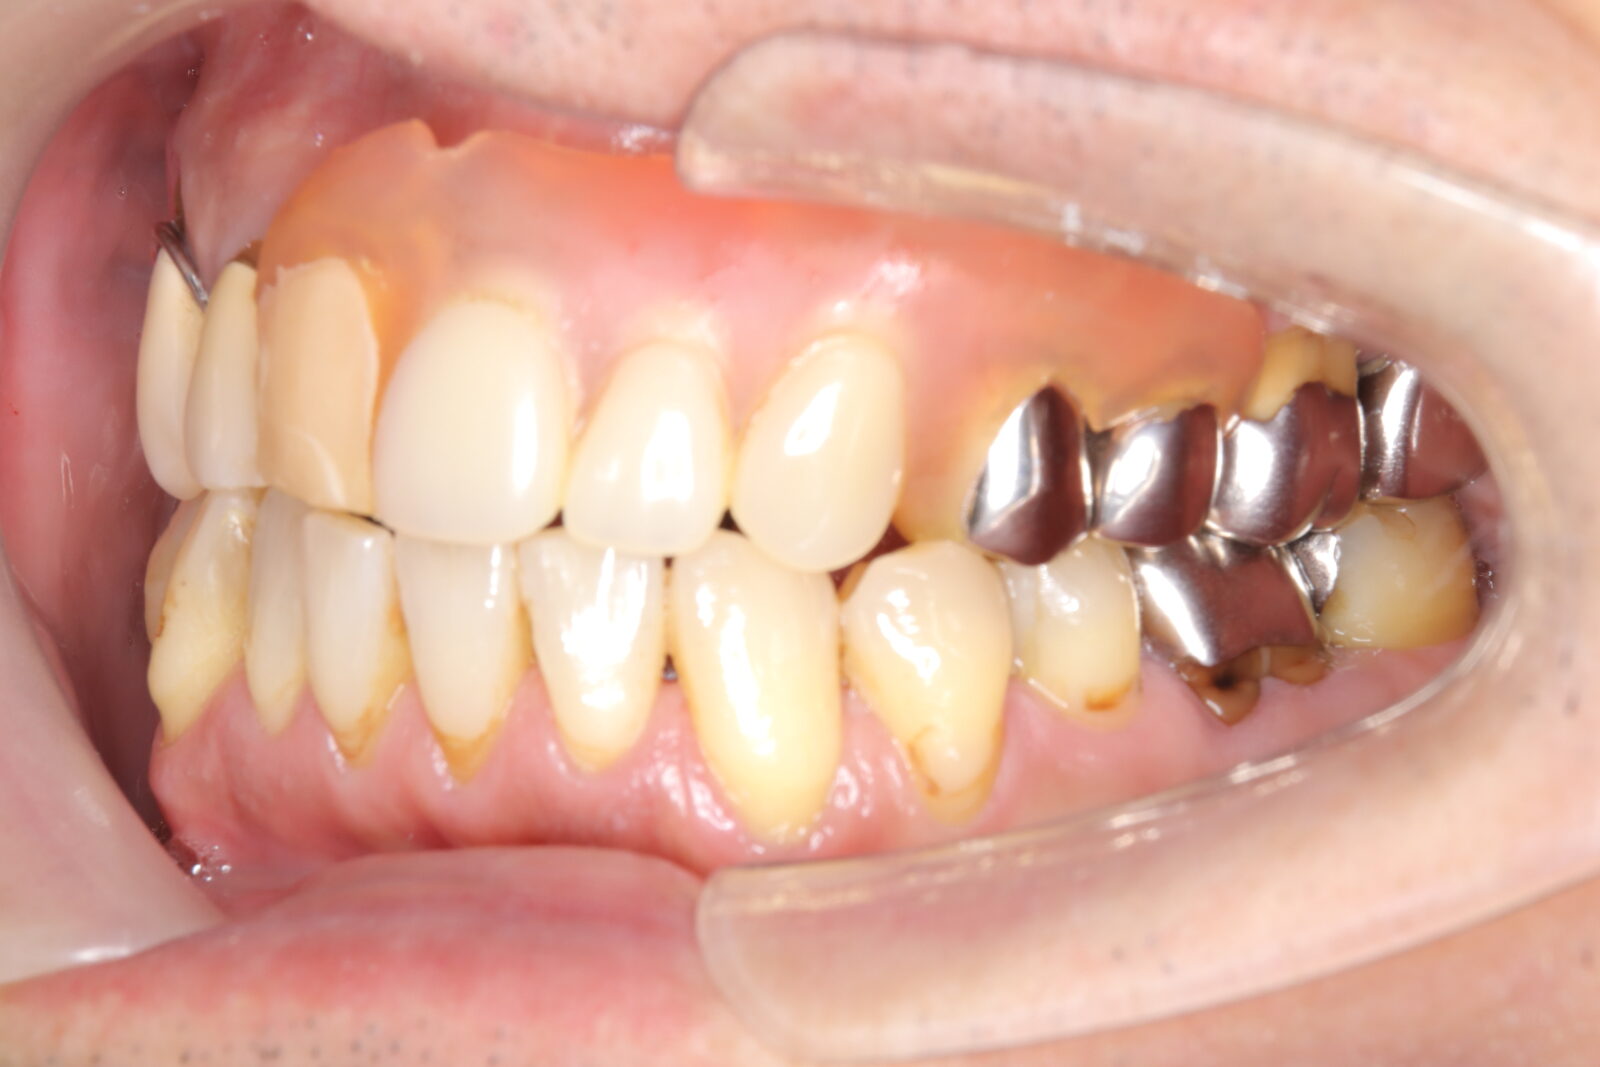

職業柄抜歯をすることができない患者様の症例

職業柄抜歯をすることができないため、小臼歯も親知らずも非抜歯の矯正となりました。 それでは歯を並べるためのスペースを確保できない。歯根の形状を分析し、可能な限り歯冠修復で前歯のサイズを小さくして、歯を動かすためのスペースを作り矯正をスタートした。 下顎前歯歯並びきれないこと、理想的な噛み合わせの獲得は難しいことをご理解いただき治療スタートした。 終了時に初期時の不自由がないことを確認済み。